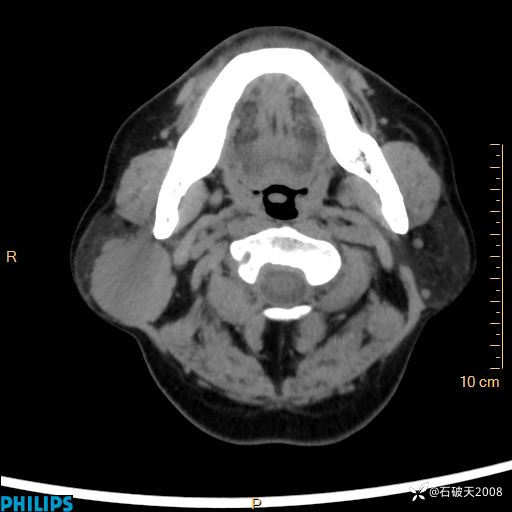

病例分享:颈部占位,一周后公布病理

男 57岁 主 诉:发现右侧颌下肿物1月余。

现病史:1月余前家属发现右侧颌下肿物。局部皮肤无红肿、热痛,无吞咽困难,无异物感,无恶心、呕吐,无头痛、头晕,无胸闷、胸痛,无发热、咳嗽、咳痰及呼吸困难。于我院行体表肿块彩超检查(2024.03.15我院)示:右侧耳下皮下软组织内低回声,未治疗。今为进一步治疗门诊以“腮腺肿瘤”为诊断收住我科,发病来患者神志清,精神可,饮食、睡眠及大小便正常,体重无明显下降。

MIP